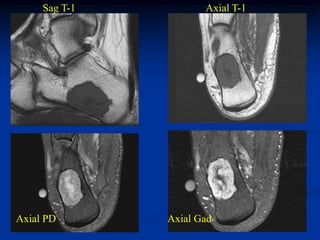

Case #649.1             Chondromyxoid fibroma os calcis

44 year old male with heel pain 1 year

Sag T-1          Axial T-1

Axial PD       Axial Gad